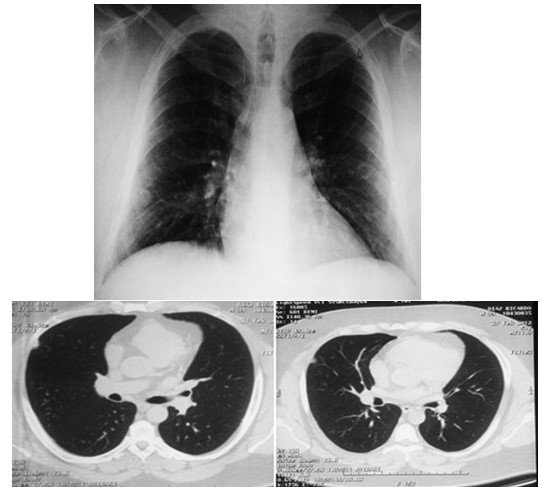

Paciente masculino de 41 años de edad, sin antecedentes médicos de importancia, quien consulta a la unidad de neumonologia por presentar procesos respiratorios de vías bajas en los últimos meses caracterizado por tos no productiva acompañada de dolor torácico, motivo por el cual se le indica radiografia de torax en donde se descubrió una imagen tipo nodular periférica en el 1/3 medio del pulmón derecho, de 1 cm de diámetro aproximadamente, sin calcificaciones en su interior y bien delimitado (Figura 1). Motivo por el cual se solicita tomografia computada torácica, donde con tomógrafo Multidetector VCTXT64® se confirmó la lesión nodular localizada a nivel de segmento lateral de lóbulo pulmonar medio que mide aproximadamente 11 mm x11 mm x 20 mm con un coeficiente 32 UH, de contornos bien definido sin calcificaciones en su interior resto del estudio sin alteración, conclusión: nódulo pulmonar (Figura 2). La exploración física era normal, asi como las pruebas analíticas elemental de sangre, orina, serología para el virus de la deficiencia humana, la exploración funcional respiratoria presentaba valores dentro de la normalidad. La reacción de Mantoux fue negativa a las 72 h. El cultivo, la coloración de Zielh-Nilzzen y el cultivo de esputo fueron negativos. Por lo cual es referido al servicio de cirugía de tórax para su evaluación y decisión de conducta terapéutica; el examen físico practicado se encontró dentro de límites normales, en vista de los hallazgo radiológicos y el examen físico la cual indicaba la presencia de patología inflamatoria, se decide dar conducta expectante con seguimiento con controles radiológicos, 14 meses después de la radiografia inicial, se aprecia aumento de dicha lesión con un diámetro de 3 cm aproximadamente (Figura 3), se realiza estudio tomografico multicorte 64 se confirma imagen de patrón nodular localizada a nivel de segmento lateral de lóbulo pulmonar medio que mide 2,5 cm x 1,8 cm de diámetro anteroposterior y transversal con un coeficiente de 27 UH, con presución diagnostica de nódulo subpleural en relación con mesotelomia (Figura 4).